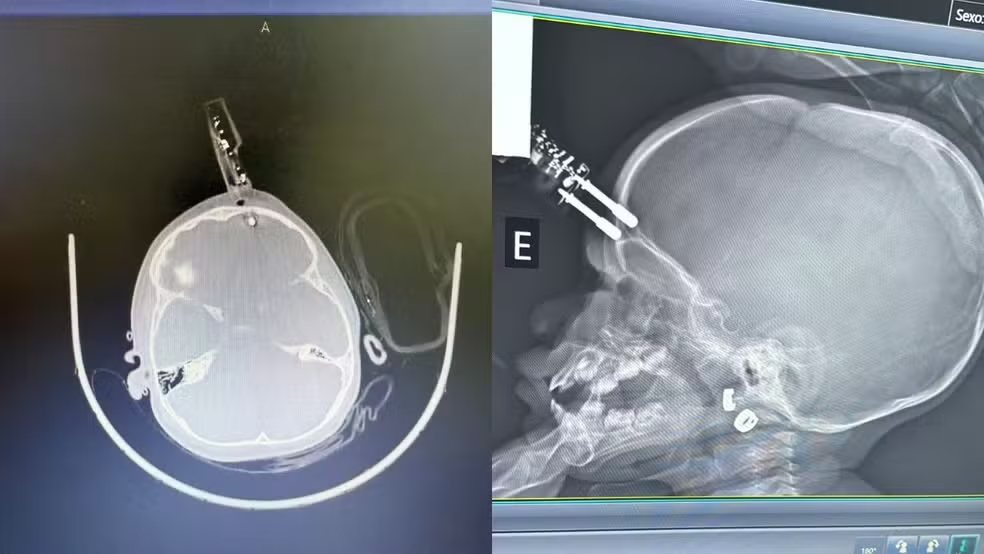

Uma menina de apenas 1 ano precisou passar por uma cirurgia de urgência após sofrer um grave acidente doméstico em Divinópolis. A criança caiu da cama e acabou ficando com um carregador de celular cravado na testa. Ela segue internada em observação e, até o momento, não apresenta sinais de sequelas neurológicas, segundo informou o neurocirurgião responsável pelo atendimento, Bruno Castro.

De acordo com o médico, o acidente aconteceu na última terça-feira (13), no momento em que a mãe teria ido ao banheiro. A principal hipótese é que a menina estava segurando o carregador quando caiu da cama. Durante a queda, o objeto atingiu a região frontal do crânio, próximo ao olho, perfurando o osso.

A criança foi levada imediatamente para o centro cirúrgico, onde passou por procedimentos de limpeza, retirada do objeto, lavagem, fechamento e reconstrução da área atingida.

Segundo Bruno Castro, o principal risco em casos como esse é a lesão cerebral. O objeto perfurante atravessou o osso do crânio e atingiu o tecido cerebral, o que poderia provocar hemorragia.